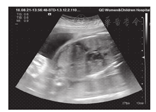

常规消毒铺巾,术前胎心率155次/min。连续超声引导下显示胎儿右心房、房间隔及左心房,确定穿刺部位为贴近探头指示点,选择18G穿刺针,针尖依次经孕妇腹壁、子宫壁、胎儿胸壁、右心房通过卵圆孔上方约5 mm打孔进入左心房(图2),然后停于左肺静脉口附近,针尖运动全程在超声图像追踪下进行。撤出针芯,沿着0.014英寸冠脉导丝(Abbott公司,美国)送入Boston Science 2.0 mm×10.0 mm冠脉球囊扩张穿刺孔,术毕连同球囊一并撤出扩张系统。手术时间15 min,术中未见明显胎儿心律失常、心包积液。